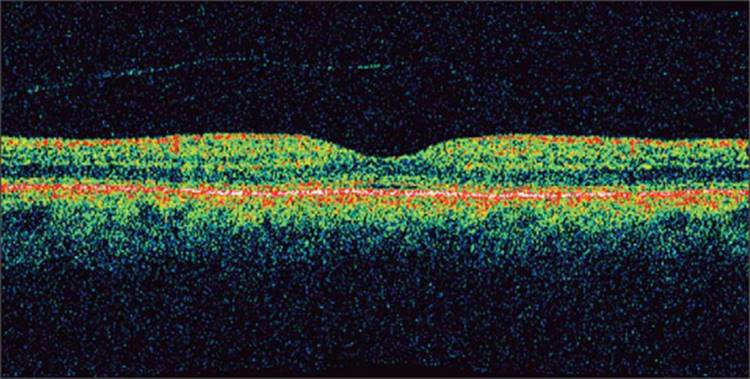

Nonexudative ARMD

Nonexudative ARMD can lead to changes in the macula such as RPE hyper- and hypopigmentation as well as basal laminar and basal linear deposits. RPE hyperpigmentation can cause increased reflectivity of the external band on OCT while RPE atrophy results in hyperreflectivity of structures deep to the RPE/choriocapillaris (Fig. 130.21).[91] Drusen will often produce a stippling effect of the external band consistent with deposits along Bruch's membrane.[92]

FIGURE 130.21 Geographic atrophy associated with ARMD. There is increased reflectivity of deeper structures centrally due to RPE atrophy beneath the fovea. Irregularities of the RPE/choriocapillaris complex on the right side of the scan are representative of drusen.